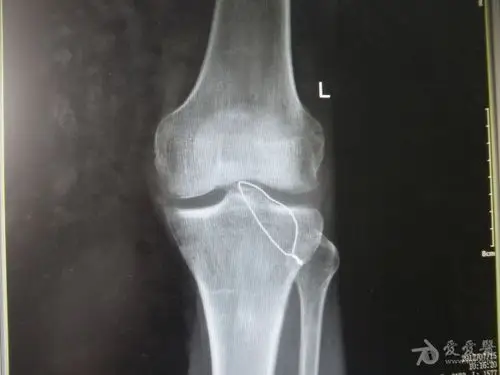

股骨大转子疼痛综合征mr特征

(1)股骨颈,转子间骨折ppt

致左膝关节肿胀,活动受限一天入院,入院诊断为:左胫骨髁间棘撕脱骨折